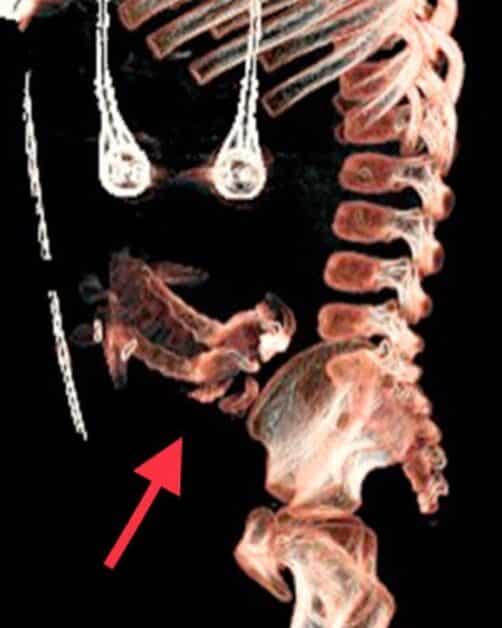

腫塊裡面,包含了一條相對完整的脊椎連接著骨盆,以及發育初期的四肢,但並沒有頭骨的構造。這個腫塊的血液供應來自男童的下肢血管分生。

醫師意識到,這是一個「胎中胎(fetus in fetu)」的病患。